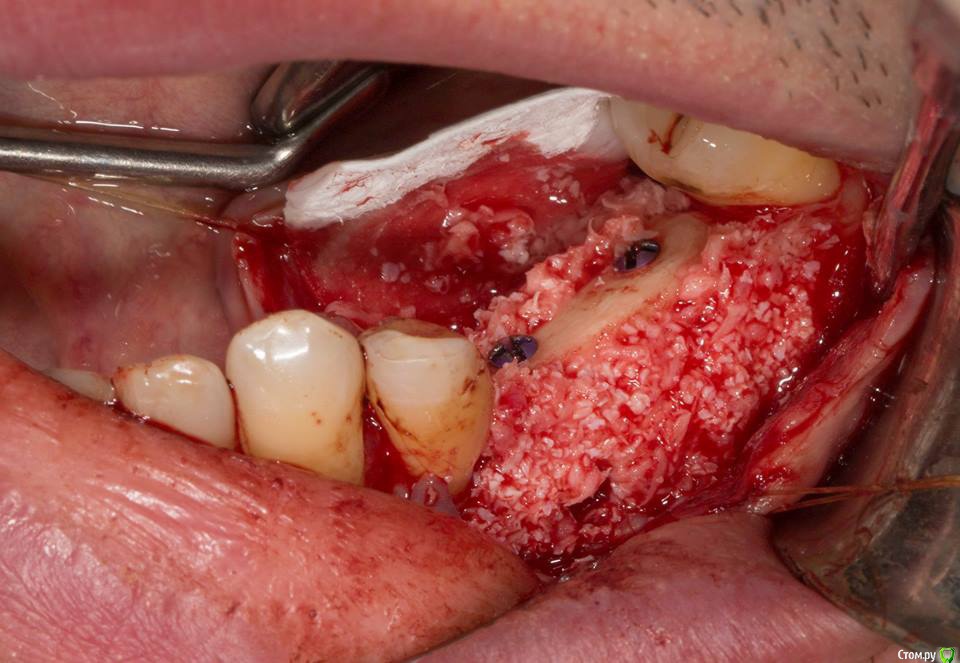

Andre_ Опубликовано 4 апреля, 2017 Поделиться Опубликовано 4 апреля, 2017 Коллеги, как раз пользуясь случаем, про "вертикаль" : делал 3д пластику, 4й сегмент. Вестибулярно аллоблок, окклюзионно - ламинат (ауто с косой много взять не вышло - было удаление лютой ретенции). 5е сутки расходятся швы, толстые щёки пациентки и не сильная мобилизация дали знать. Помыл хлориком пару суток и решил завтра вынимать. Как считаете, есть смысл оставить, например, вестибулярный аллоблок, отмыв инфицированный графт? или лучше выносить всё?Какой вариант для повторной операции лучше выбирать на н/челюсти в боковом отделе? Ссылка на комментарий

kamranchick Опубликовано 4 апреля, 2017 Поделиться Опубликовано 4 апреля, 2017 Коллеги, как раз пользуясь случаем, про "вертикаль" : делал 3д пластику, 4й сегмент. Вестибулярно аллоблок, окклюзионно - ламинат (ауто с косой много взять не вышло - было удаление лютой ретенции). 5е сутки расходятся швы, толстые щёки пациентки и не сильная мобилизация дали знать. Помыл хлориком пару суток и решил завтра вынимать. Как считаете, есть смысл оставить, например, вестибулярный аллоблок, отмыв инфицированный графт? или лучше выносить всё?Какой вариант для повторной операции лучше выбирать на н/челюсти в боковом отделе?Когда идет инфицирование надо смотреть откуда оно идет, скорее всего погибнет все к едрени фени, тем более алло, я бы убрал бы. через 2 месяца повторно сетка. Ссылка на комментарий

Andre_ Опубликовано 5 апреля, 2017 Поделиться Опубликовано 5 апреля, 2017 Когда идет инфицирование надо смотреть откуда оно идет, скорее всего погибнет все к едрени фени, тем более алло, я бы убрал бы. через 2 месяца повторно сетка.спасибо, посмотрел ещё раз контроль КТ, думаю всё выгрести. Ссылка на комментарий